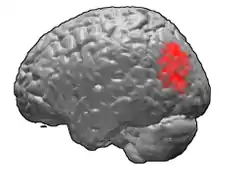

Brodmann area 39

Brodmann area 39, or BA39, is part of the parietal cortex in the human brain. BA39 encompasses the angular gyrus, lying near to the junction of temporal, occipital and parietal lobes.

This area is also known as angular area 39 (H). It corresponds to the angular gyrus surrounding the caudal tip of the superior temporal sulcus. It is bounded dorsally approximately by the intraparietal sulcus. In terms of its cytoarchitecture, it is bounded rostrally by the supramarginal area 40 (H), dorsally and caudally by the peristriate area 19, and ventrally by the occipitotemporal area 37 (H) (Brodmann-1909).